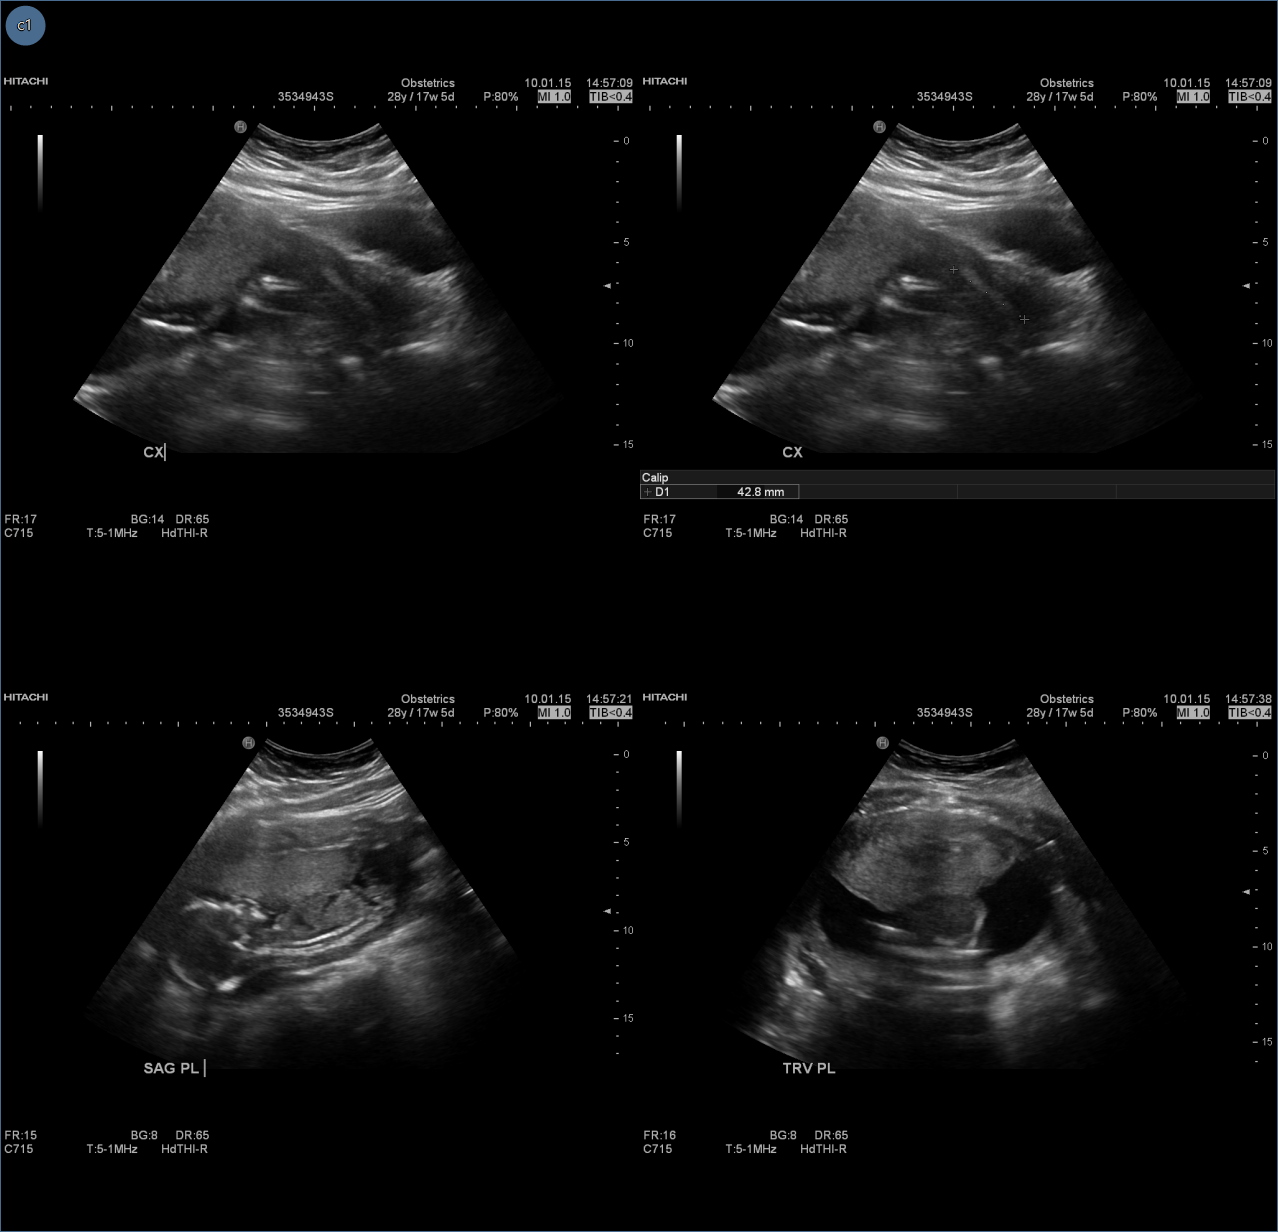

The Grids matrix, by default, will split the screen into symmetrical groups of image frames. When the Grids matrix ![]() is selected in the tools group, a drop down panel appears showing open frames.

is selected in the tools group, a drop down panel appears showing open frames.

Dragging the mouse from the top left corner down will allow the user to draw or define a generic layout for the image frames. The image above shows the frames in a 2 x 3 layout with the frames highlighted red.